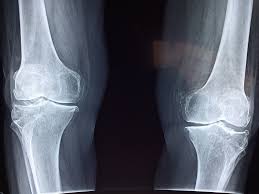

Un détail souvent négligé concernant les sodas, surtout les colas, c’est leur influence sur la solidité des os. Le problème ne vient pas d’un composant en particulier, mais plutôt du fait qu’ils prennent souvent la place de boissons riches en calcium, comme le lait ou les boissons végétales enrichies. Pour les ados et jeunes adultes, ce remplacement peut nuire à la construction d’une charpente osseuse solide. Chez les adultes, cela peut accélérer une perte minérale progressive au fil du temps.